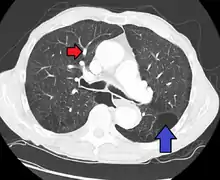

CT scan

Signs of pulmonary hypertension on CT scan of the chest are:

- Enlargement of the pulmonary trunk (measured at its bifurcation). It is, however, a poor predictor of pulmonary hypertension in patients with interstitial lung disease.[60]

- A diameter of more than 27 mm for women and 29 mm for men is suggested as a cutoff.[60]

- A cutoff of 31.6 mm may be a more statistically robust in individuals without interstitial lung disease.[60]

- Increased ratio of the diameter of the main pulmonary artery (pulmonary trunk) to the ascending aorta (measured at its bifurcation).

- Increased diameter ratio of segmental arteries to bronchi. This finding in three or four lobes, in the presence of a dilated pulmonary trunk (≥29 mm), and absence of significant structural lung disease confers a specificity of 100% for pulmonary hypertension.[60]

- Mural calcification in central pulmonary arteries is most frequently seen in patients with Eisenmenger's syndrome.[60]